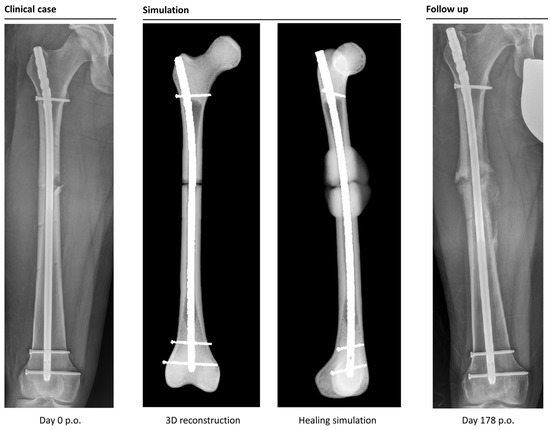

The simulation classified 26 cases as “healing”, while it categorized 6 cases as non-unions. In retrospective comparison with the clinical outcomes, the simulation correctly predicted 23 uncomplicated healing fractures. Three patients would have been expected to heal according to the simulation, but clinically turned out as non-unions (false negatives). Four out of six predicted non-unions were correctly recognized by the simulation, but two cases were wrongfully diagnosed as developing non-unions (false positives). This means the simulation correctly predicted the right outcome in 85% of the cases (Figure 4 and Figure 5).

Figure 4. Example of a correctly simulated, healing fracture. The postoperative X-ray (picture 1, left) is used to build a 3D reconstruction (picture 2). The simulation correctly predicts uncomplicated healing (picture 3). A retrospective comparison to a follow-up X-ray on day 168 after surgery shows similar callus formation and progressing consolidation (picture 4, right).

Figure 5. Example of a correctly simulated non-union fracture. The postoperative X-ray (picture 1) is used to build a 3D reconstruction (picture 2). The simulation correctly predicts a biomechanically induced non-union (picture 3). A retrospective comparison to a follow-up X-ray on day 178 after surgery shows similar callus formation and no healing, resulting in a consecutive revision surgery (picture 4).